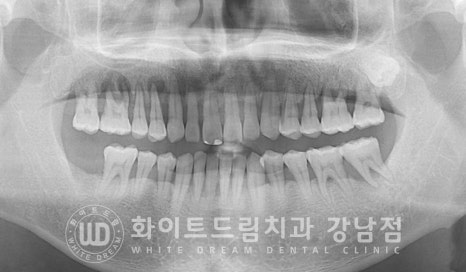

환자분의 초진 x-ray 사진입니다.

전체적으로 잇몸뼈가 치주염으로 크게 내려앉아있는 상태로

치료가 필요한 부위가 많이 있으나

한 번에 치료를 진행하기보다는 천천히 하나씩 진행하길 원하셔서

우선적으로 불편함을 크게 호소하셨던 10번대 어금니부터 치료를 진행하고 계신 분입니다.

10번대 치아 주위 잇몸뼈를 보면 검은색으로

치아 뿌리 주위에 동그랗게 표기된 부분이 보일 겁니다.

x-ray 상에서 밀도가 낮을수록 이렇게 검은색으로 나타납니다.

원래는 잇몸뼈가 있어 하얗게 보여야 하는 부위인데

잇몸뼈가 녹고 그 자리에 액체(고름)이 차있는 상태라고 보시면 되겠습니다.

이 치아들은 잇몸뼈가 아닌 고름이 치아의 대부분을 잡고 있는 상태로

동요도 검사 시에도 심하게 상하좌우로 흔들리고 있는 것이 확인되었고

환자분도 식사를 할 때마다 통증과 치아의 흔들림이 느껴지신다고 하여

발치 즉시 임플란트 치료를 진행하기로 치료 계획을 세웠습니다.